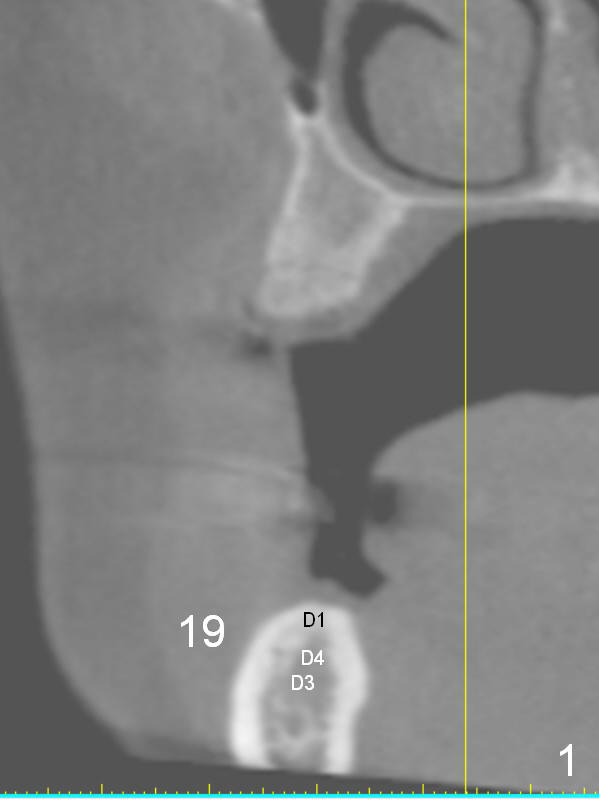

A 49-year-old lady is petit. The crest at #30 is narrow. A small implant is placed. To increase its longevity, the patient should have left 1st molar occlusion. Bone density at #19 is D1 (the cortex), D4 (upper medulla) and D3 (lower medulla) (Fig.1). Bone is wide enough to hold a 6 mm (in diameter) implant, but a 8 mm long implant appears to be too long (Fig.2). Therefore, a 6 or 6.5x6 mm implant appears to be appropriate (Fig.3). How about the bone at #14?